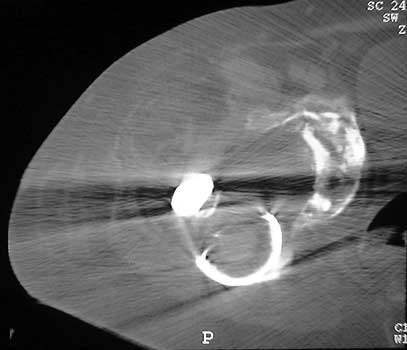

Dislocated femoral component and acetabular cup in grossly loose arthroplasty. CT guided aspiration to rule out infection.